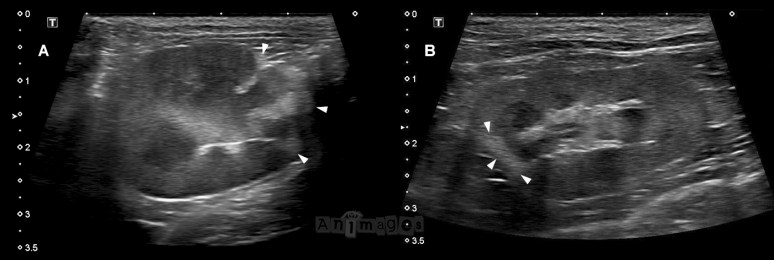

Les images ci-haut provenant de deux chats différents illustrent bien l’apparence classique de ces infarcti. Notez l’atrophie consécutive de la section hyperéchogène du cortex atteint, déformant le contour du rein. Le clip ci-bas permet d’apprécier le rein en A de façon dynamique. Ce chat ne présentait pas de souffle cardiaque au moment de l’examen, mais une échographie cardiaque n’a pas été réalisée pour exclure plus définitivement une cardiomyopathie sous-jacente. Le chat en B avait quant à lui une cardiomyopathie hypertrophique confirmée.